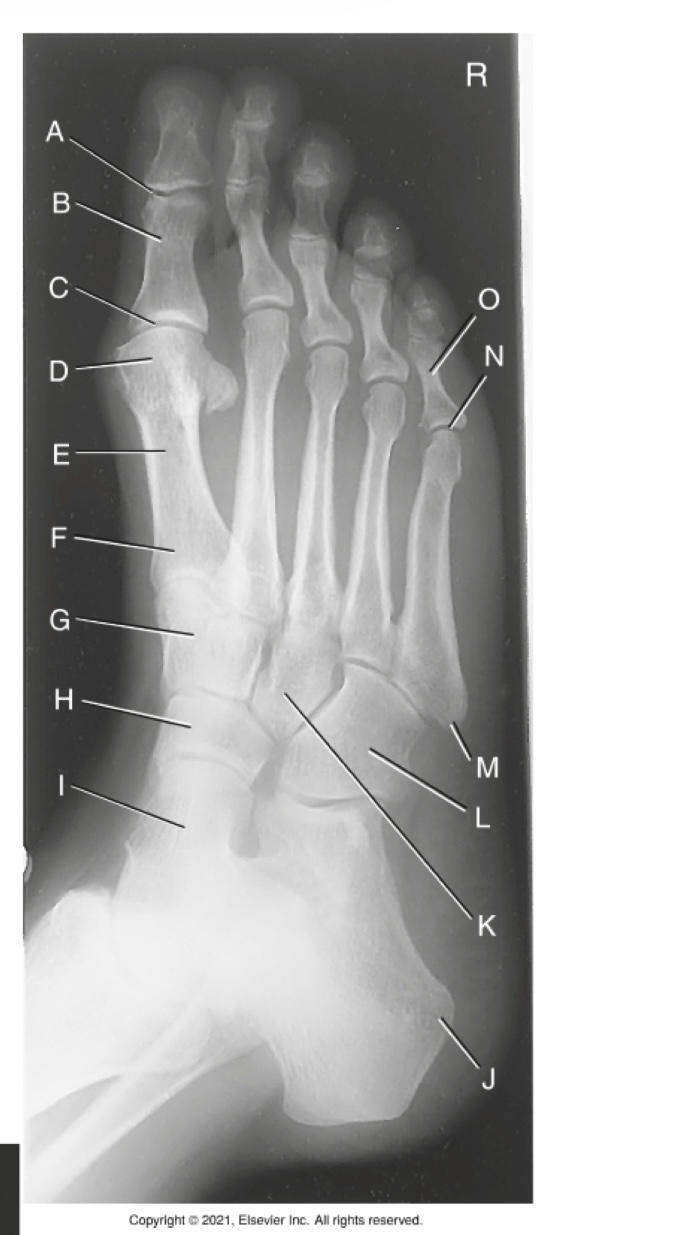

A

Interphalangeal joint of 1st digit

B

Proximal phalanx of 1st digit

C

Metatarsophalangeal joint of 1st digit (MTP joint)

D

Head of 1st metatarsal

E

Body of 1st metatarsal

F

Base of 1st metatarsal

G

Second/ intermediate cuneiform

H

Navicular

I

Talus

J

Tuberosity of calcaneus

K